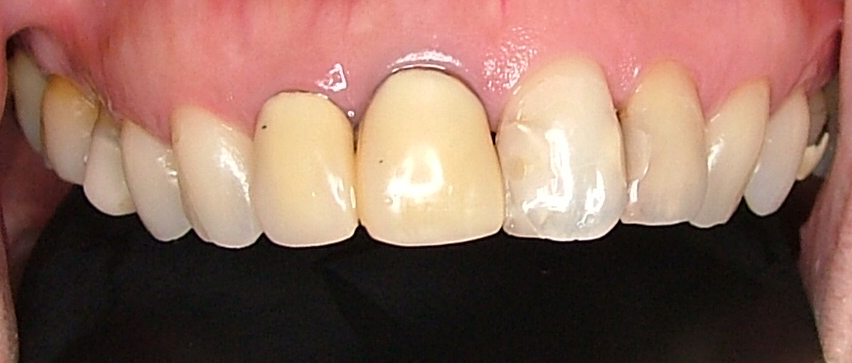

| 治療内容 | ジルコニアセラミック |

|---|---|

| 治療回数 | 3回 |

| 治療時の費用 | 330,000円(税込) ※本症例当時の価格です。最新の費用はこちら |

| リスク・副作用 | 乱暴なブラッシングをすると歯肉が退縮する可能性があります。 |